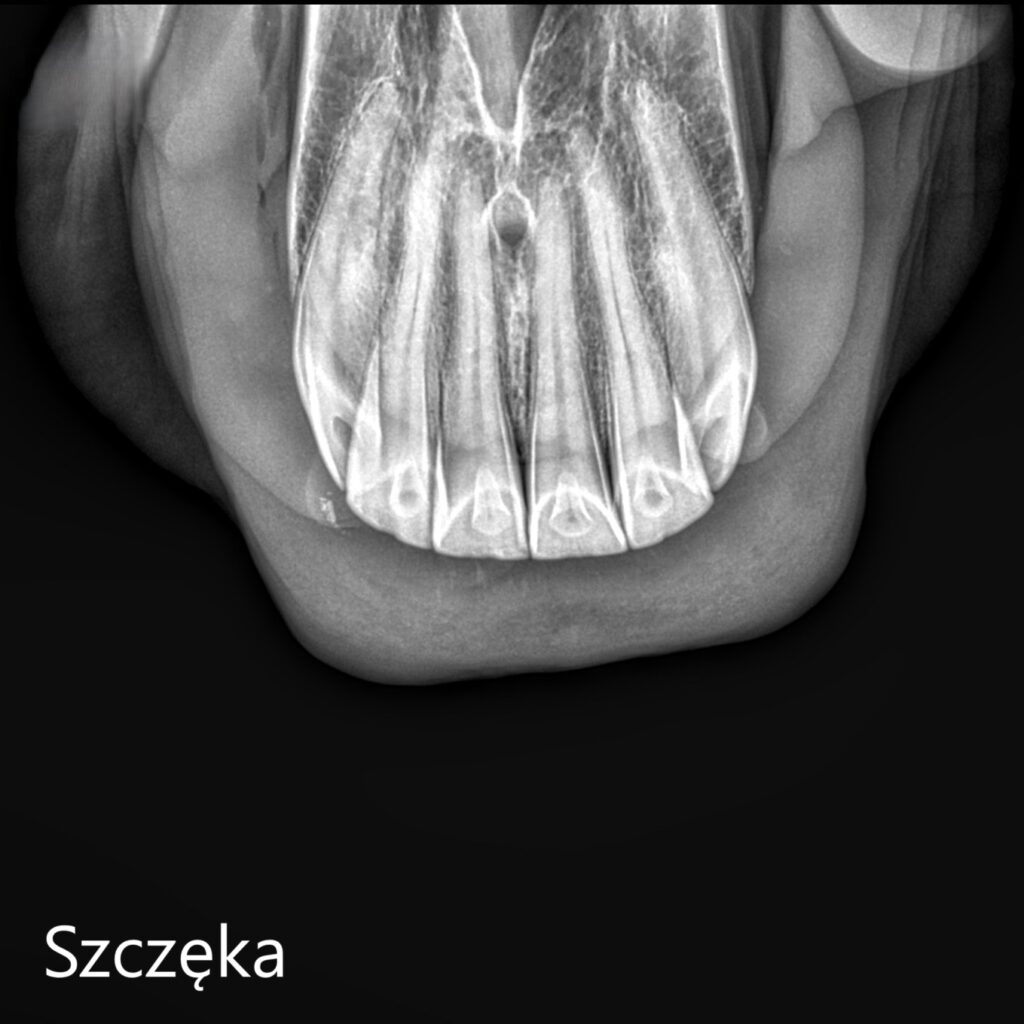

W przypadku koni starszych lub koni z podejrzeniem chorób zębodołów, infekcji czy resorpcji zębów, warto uzupełnić badanie kliniczne o kontrolne zdjęcie RTG. Radiografia pozwala na wykrycie zmian niewidocznych gołym okiem i zaplanowanie odpowiedniego leczenia.